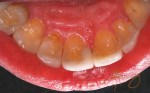

When passion becomes your profession..making people smile becomes your habit! here’s my recent case of cosmetic dentistry: